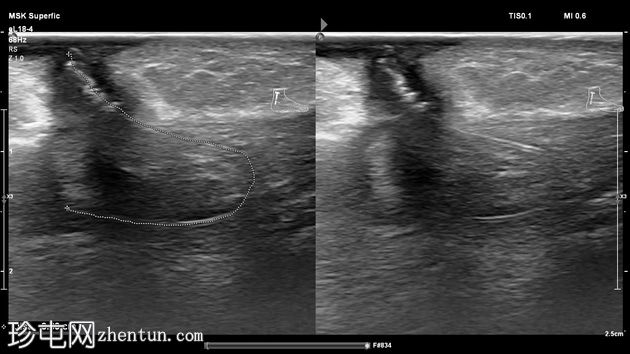

超声检查

3.jpg

纵位

左足跟皮下组织内可见一管状高回声物质,呈串珠状,与手术缝线相符,周围环绕着低回声积液。与缝线相连的是一根细细的、呈轨道状的高回声合成单丝,它穿过跟腱呈弧形走行,该缝线为不可吸收缝线。